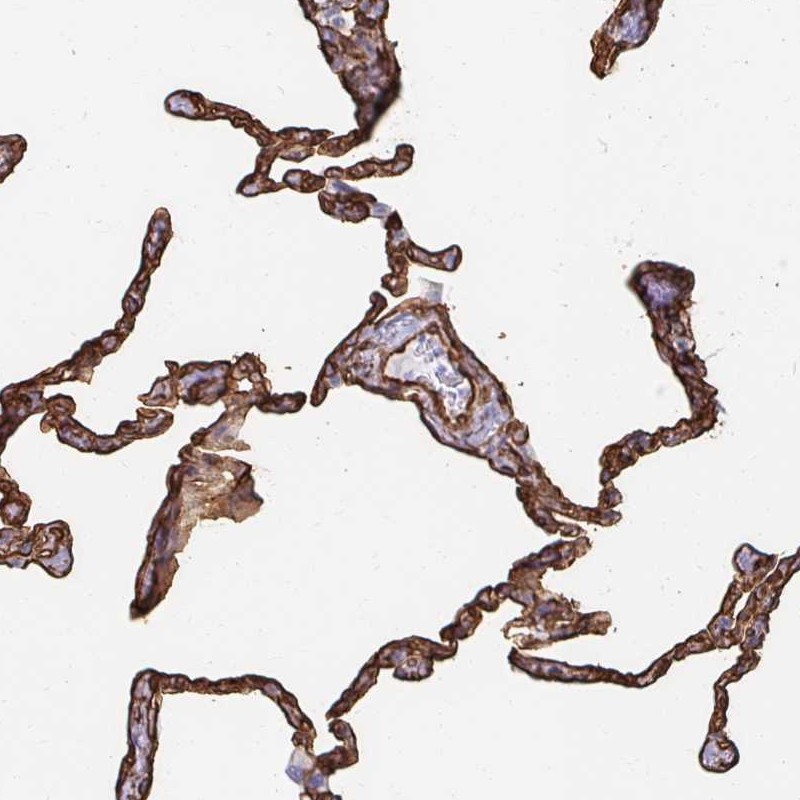

Immunohistochemical staining of human lung shows strong cytoplasmic positivity in pneumocytes.